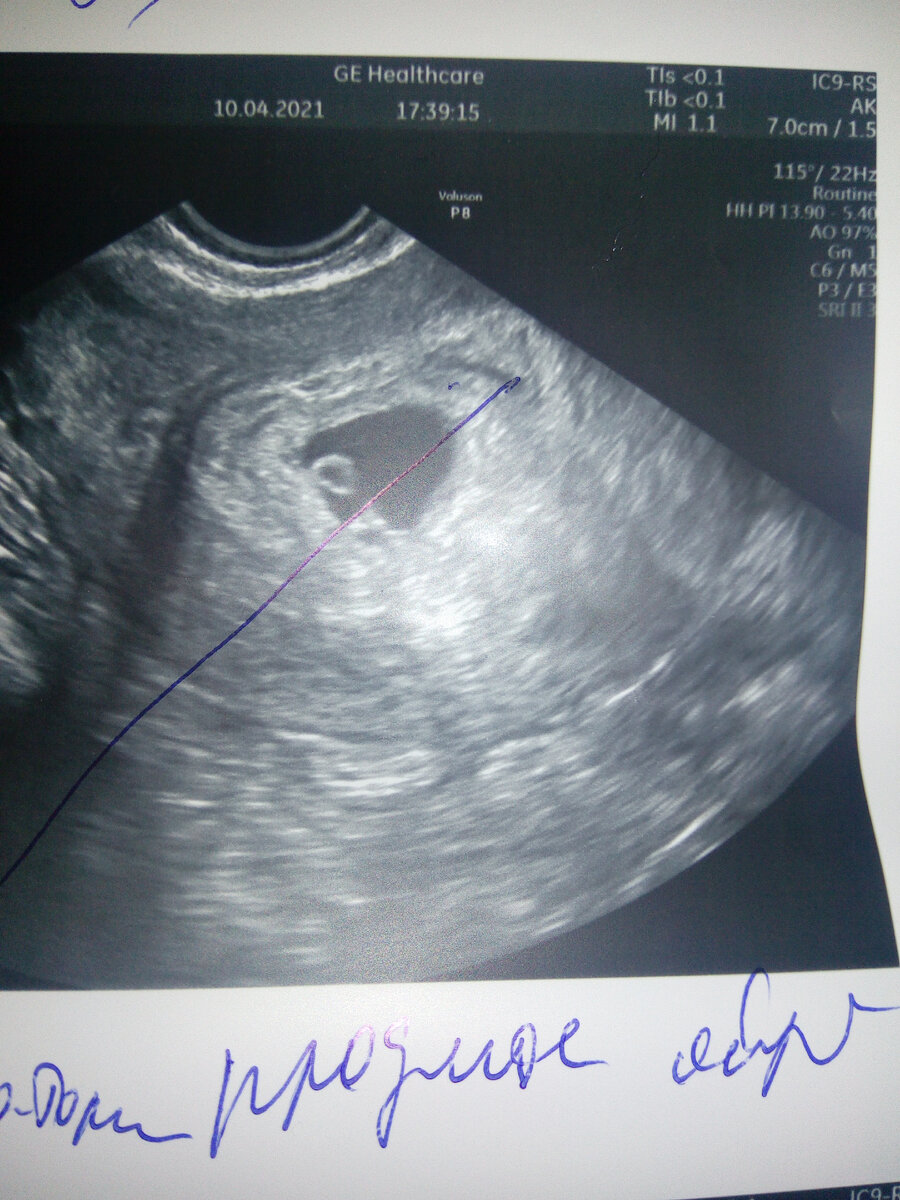

И вот, когда пошла на первое УЗИ, после двух заветных полосок, мне подтвердили беременность и сразу сообщили об угрозе. Из-за поднятия тяжести у меня образовалась гематома.

Вот она "красавица"

Посмотрев, что гематома увеличилась, врач меня поспешила успокоить. Ведь плодное яйцо тоже растет, а значит и отслойка увеличивается. Главное, чтобы это было пропорционально. Ещё меня предупредили, что возможны темные выделения, так как она будет рассасываться, и предложили полежать в дневном стационаре.